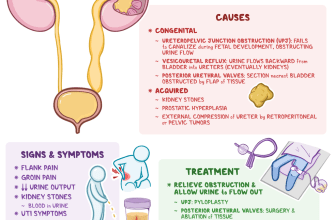

Kidney malformations, also known as kidney abnormalities

Kidney stones are a common condition that affects millions

Kidney stones are a common and painful condition that

Kidney tumors, also known as renal tumors, are abnormal